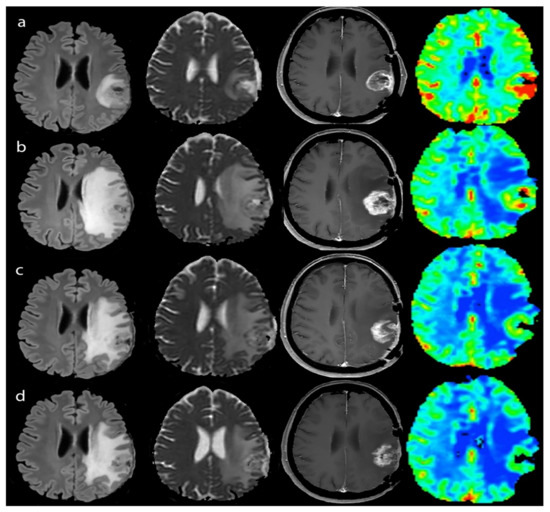

2.3.2. Perfusion

2.3.3. Diffusion

3.2.1. Response Assessment